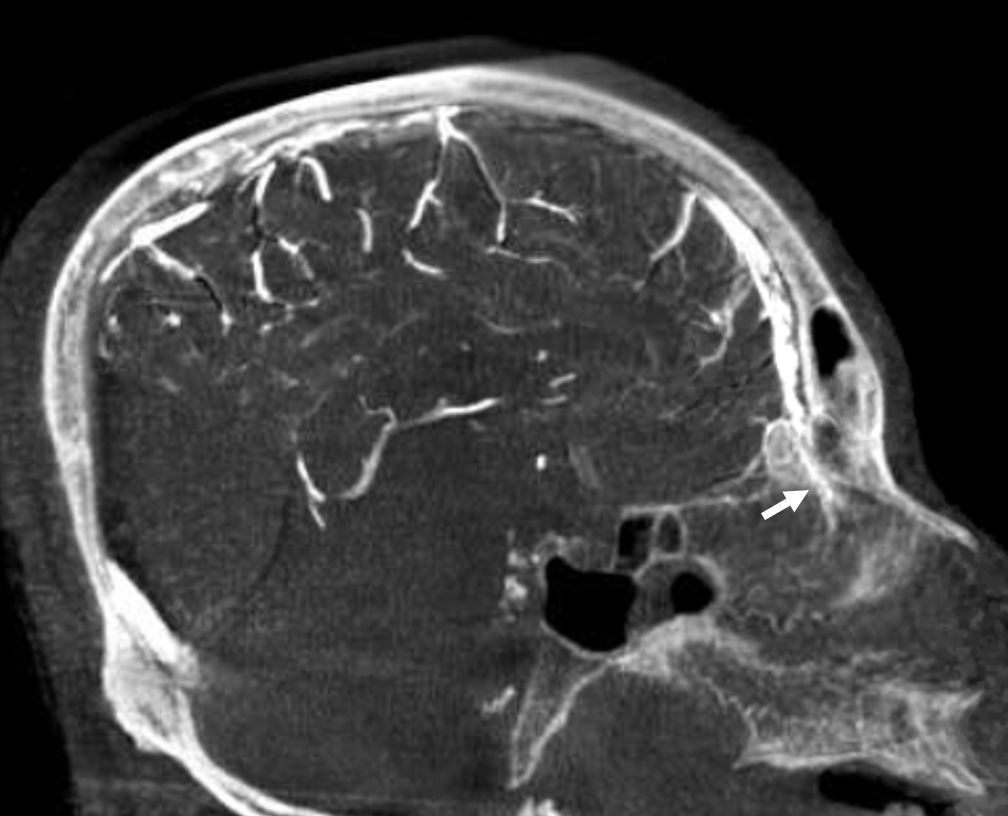

The sigmoid sinuses are not always of the same caliber as the transverse ones, especially when a large vein of Labbe empties into the proximal sigmoid sinus to enlarge it substantially as compared with its transverse tributary. Extensive emissary veins (mastoid, occipital, condylar) often drain in part and occasionally in toto the transverse-sigmoid sinus complex, and the corresponding jugulars may be hypoplastic. Isolated findings of this nature are rarely due to consequences of pathologic shunting, and looking on bone windows for emissary channels can confirm this as a non-pathologic anatomical disposition.